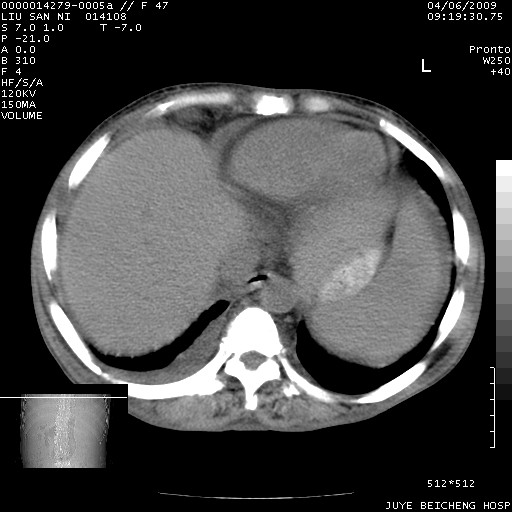

以下是引用前行在2009-4-7 10:31:00的发言:[br]肝脾肿大;双肾增大,双肾盂少量积水可能,肾膜膜增厚,肾周间隙增宽,并见桥间隔,提示结缔组系统疾病、系统性红瘢狼疮肾可能性大。继发右侧胸腔、心包、腹腔积液。